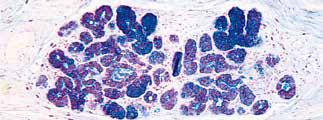

食管中段。食管黏膜由表面的上皮层、中间的固有层及下面的黏膜肌层构成,黏膜肌层由纵行平滑肌束构成。

固有层是黏膜层的非上皮部分,位于黏膜肌层之上,由疏松结缔组织构成,含有脉管结构、散在分布的炎症细胞及黏液分泌性腺体。

食管贲门型腺体弥漫散在分布于整个食管的固有层内,主要见于食管远端和近端部分。这些腺体起润滑作用,以便于食物团块顺利通过食管,这在生理上是必须的。

组织学上,这些腺体位于固有层内,与胃贲门型腺体相似,由分泌中性黏液的细胞组成。

食管贲门型腺体位于固有层内。导管内衬胃小凹样上皮细胞。

导管内衬细胞可能经过不同的距离延伸至复层鳞状黏膜上方(PAS-D)。

这些腺体呈PASD 染色阳性,pH 值2.5 的阿辛蓝染色阴性,表明具有中性黏液的特征。